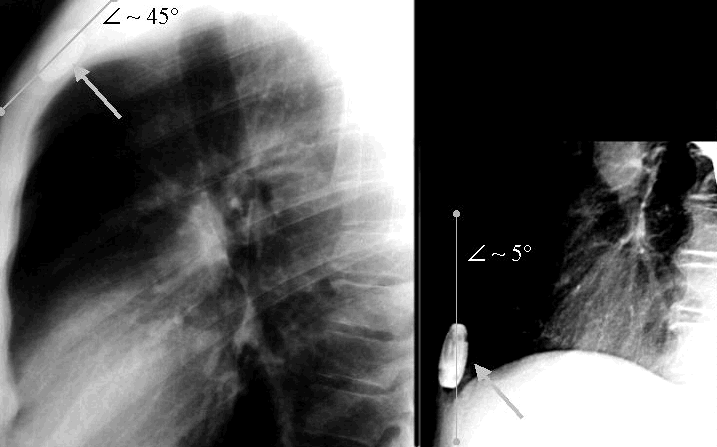

Das rechte Röntgenbild zeigt ein DSV, das im unteren Drittel des Brustkorbes implantiert ist. Es ist nahezu parallel zur senkrechten Körperachse. Entsprechend schaltet dieses Ventil auch korrekt zwischen Hoch- und Niederdruckventil um, wenn der Patient seine Körperposition ändert. Das linke Röntgenbild zeigt ein DSV, das an einer anderen Klinik implantiert wurde. Es wurde in der Nähe des Schlüsselbeins implantiert. Zur Körperlängsachse hat dieses Ventil einen Winkel von etwa 45°. Dieses Ventil kann nicht korrekt umschalten von der Nieder- zur Hochdruckseite, da selbst beim senkrechten Stehen, das Ventil noch in einer solchen Schräglage ist, dass die schaltende Tantalkugel den Abfluß aus dem Niederdruckventil nicht wie gewünscht verschließt. Nach korrekter Implantation des Ventils hatte dieser Patient keine Beschwerden mehr durch die Überdrainage, die vorher bestand.